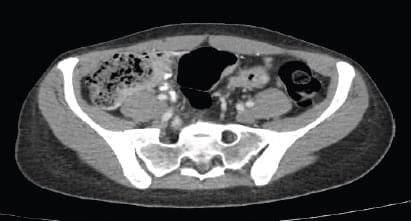

Continuó hospitalizada para completar estudios y al decimoprimer día de hospitalización presenta dolor abdominal epigástrico asociado a náuseas, dos episodios eméticos y ausencia de deposiciones, por lo que es valorada por cirugía general quienes solicitan radiografía de abdomen en bipedestación (figura 2), en la que se observa abundante materia fecal en todo el marco cólico por probable estreñimiento, sin signos de obstrucción intestinal, neumoperitoneo, ascitis, ni calcificaciones patológicas, y ecografía de abdomen que reporta leve engrosamiento de las paredes del colon sigmoide, probablemente de origen inflamatorio, e interposición de gas en marco cólico derecho.

Figura 2. Radiografía simple de abdomen con abundante

cantidad de material fecal en el marco cólico por probable

estreñimiento, sin signos de obstrucción intestinal ni neumoperitoneo.

Se decidió realizar una tomografía de abdomen (figura 3) que mostró engrosamiento concéntrico de las paredes del colon sigmoide de 7 mm de espesor, de aspecto inespecífico, de probable etiología inflamatoria, asociado a coprostasis en el colon ascendente y transverso, sin observarse adenomegalias, y endoscopia de vías digestivas altas, cuyo único hallazgo fue gastritis crónica.

Figura 3. Tomografía de abdomen con imagen de

engrosamiento concéntrico de las paredes del colon sigmoide.